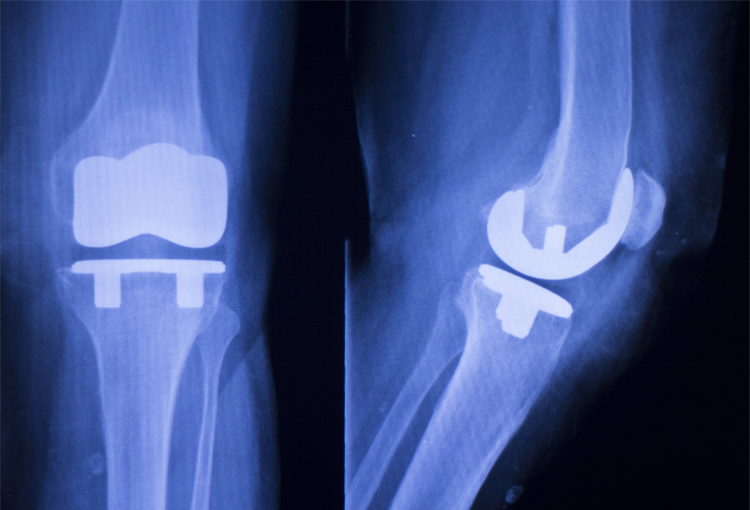

La artroplastia total de rodilla es un procedimiento quirúrgico que consiste en remplazar dicha articulación dañada colocando un implante interno artificial.

En la radiografía de la izquierda se observa la asimetría entre los espacios de la articulación de la rodilla, el lado lateral se observa separado y hacia el lado contrario se presenta un desgaste o pinzamiento entre los dos huesos que se traduce como una pérdida del cartílago o cojinete articular.

La radiografía de la derecha es la toma con la rodilla de lado que muestra desgaste entre la rotula y el fémur.